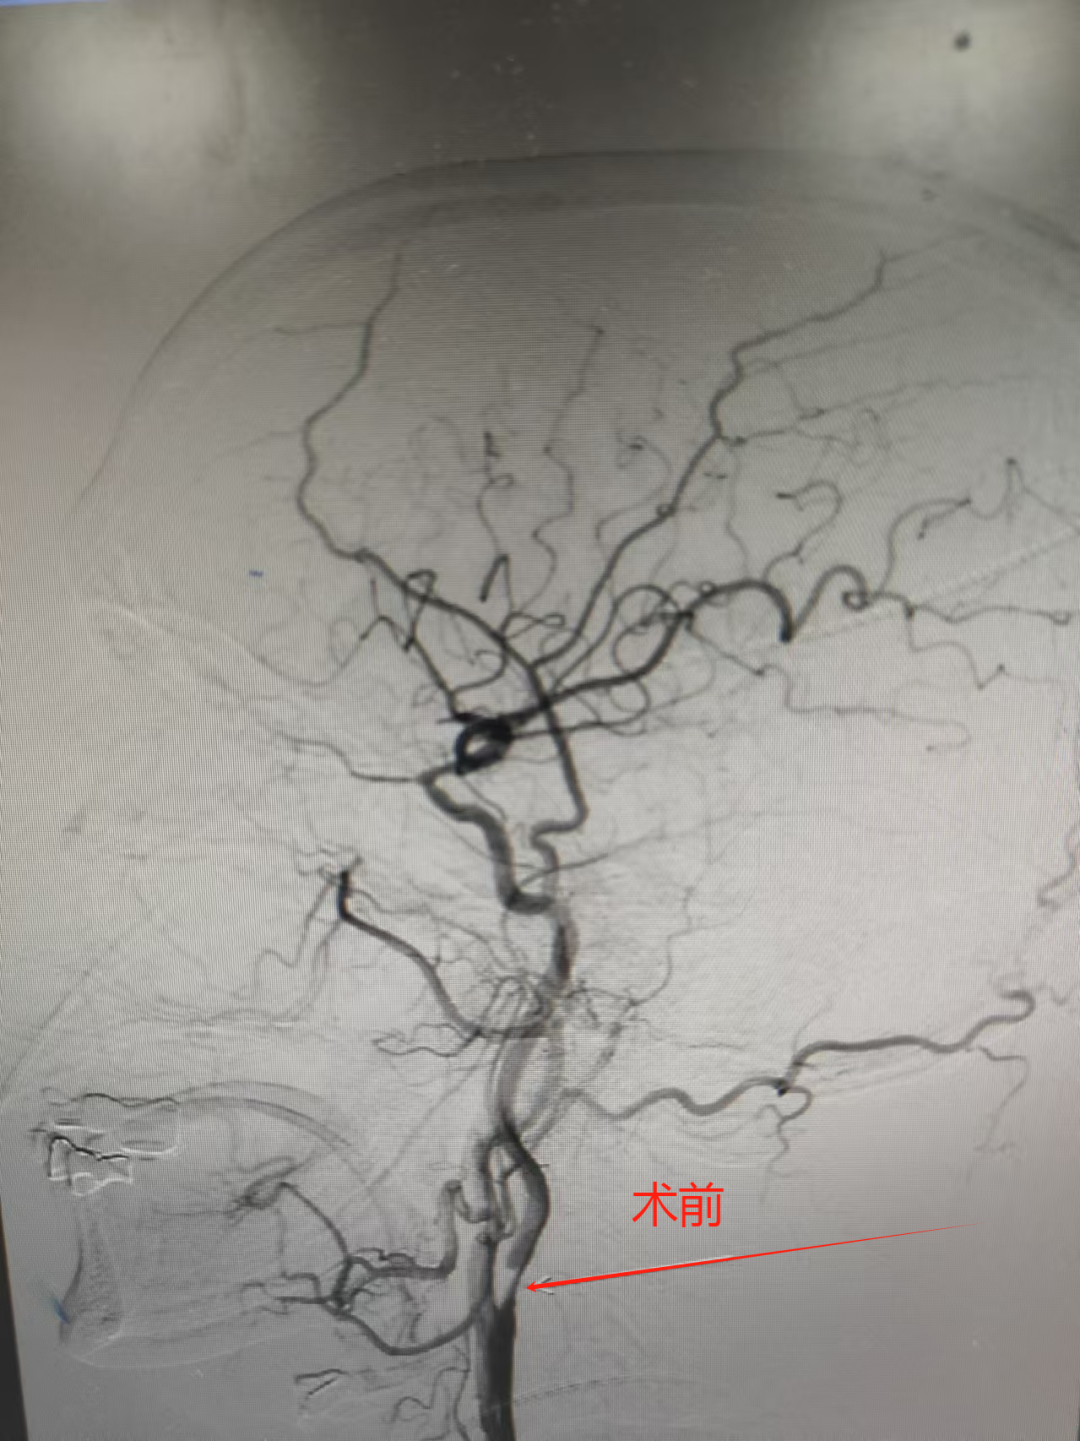

73岁王阿姨突发言语不清、说话费力,伴左侧肢体无力,持物不稳,口角歪斜。入院后经检查为急性脑梗塞,随时有猝死的风险。5分钟急诊介入取栓治疗后,效果立竿见影,当即言语清晰,左侧肢体能平稳上抬。

61岁刘大爷记忆力下降,反应大不如前且肢体乏力,经颈血管超声检查发现颈动脉重度狭窄。神经内科介入团队为其植入支架开通了狭窄的血管。术后,患者头晕、肢体乏力及反应、记忆力等情况逐渐好转。